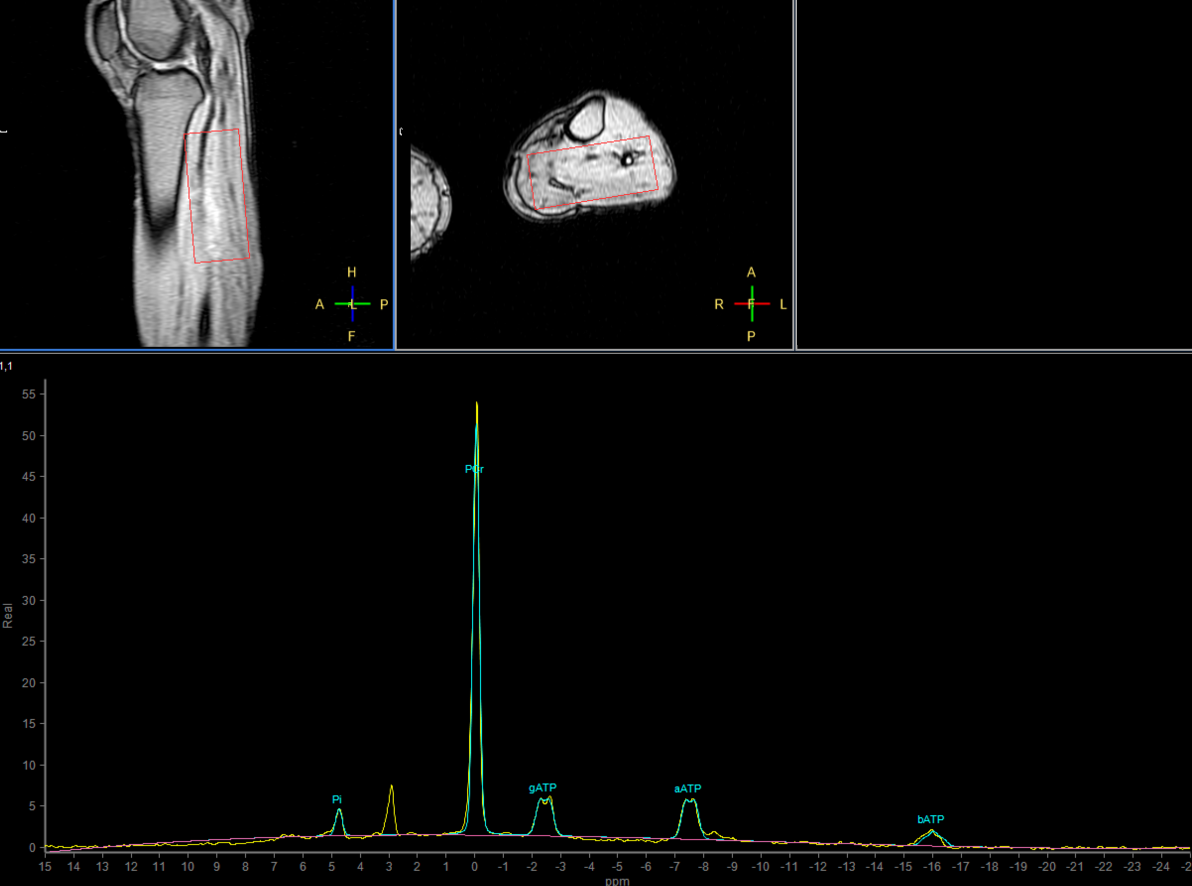

31P Phase Acquired (5 sec/acq, 50 dynamics)

31P Phase Acquired (Rest - Stress - Recovery)

31P Phase Acquired (Rest)

31P Phase Acquired (Stress)

31P Phase Acquired (Recovery)